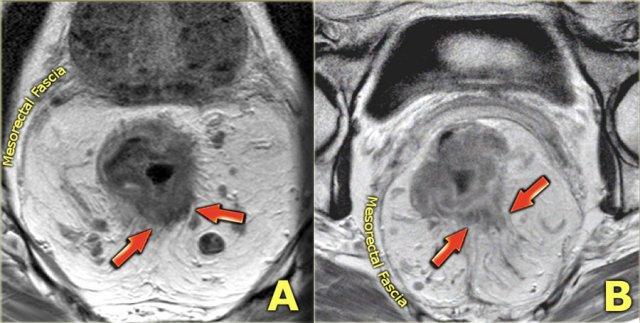

Hình ảnh

Các hình ảnh được cung cấp cho thấy ung thư biểu mô tế bào nhẫn với tình trạng dày lan tỏa thành trực tràng, hình ảnh bia bắn điển hình, và sự xâm lấn mỡ mạc treo trực tràng.